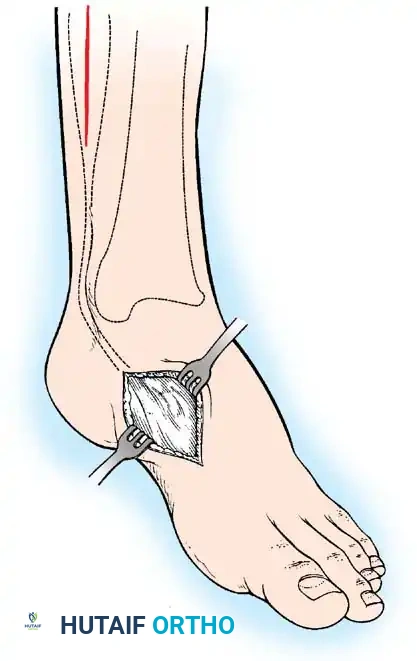

Paralytic Equinus:

Caused by paralysis of the anterior tibial muscles with sparing of the triceps surae. If dynamic, it is managed with a posterior tibial tendon transfer through the interosseous membrane to the dorsum of the foot.

Image